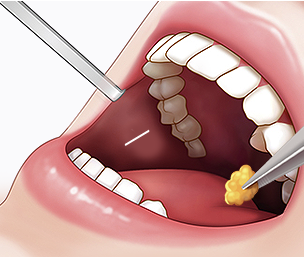

입안을 절개하여 외부 흉터 없이

심부볼 지방을 안전하게 제거합니다.

STEP 01 디자인

얼굴 골격과

STEP 02 절개

입안 점막을

STEP 03 지방 제거

심부볼 지방 덩어리를

STEP 04 봉합 및 완성

녹는 실로 꼼꼼히 봉합하여